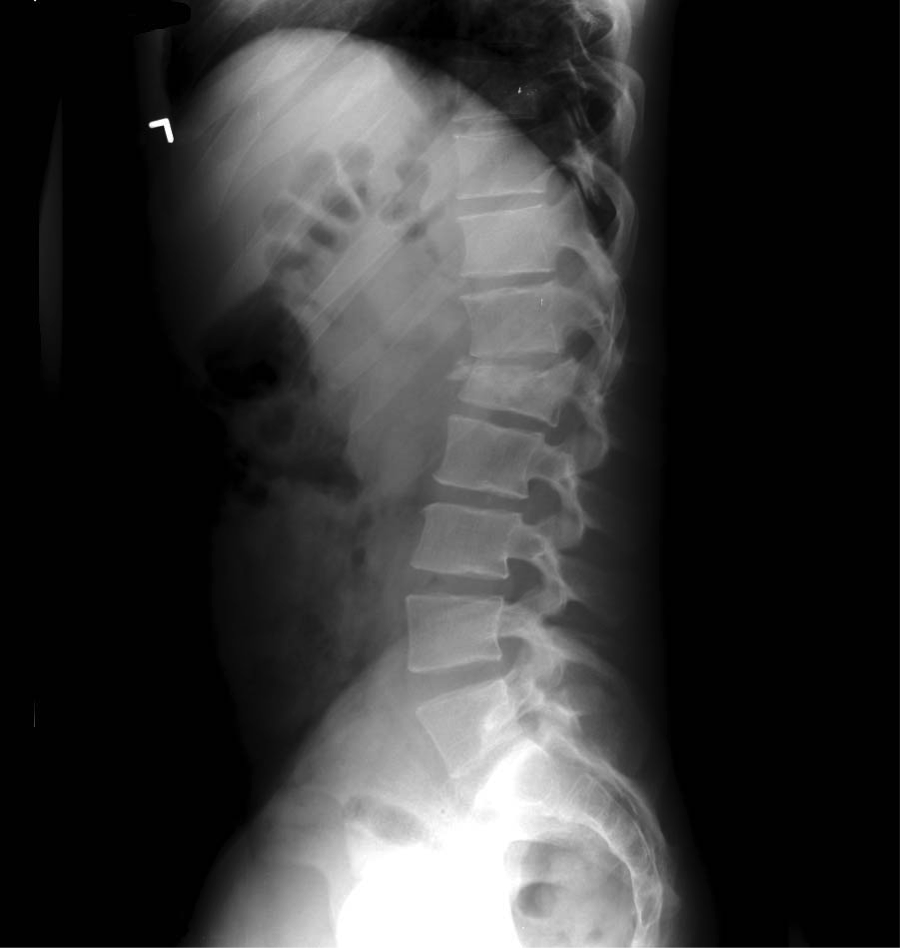

A Chance fracture is an unstable, flexion-distraction injury of the vertebral column. Pediatric Chance fractures typically present in children around 9-10 years of age following motor vehicle accidents involving lap belt restraints, with the most common injury level at L2-L3 and a high incidence of concomitant intra-abdominal injuries.

• CT Subtlety: These injuries can be subtle on axial CT slices if you aren't looking for the horizontal fracture line through the vertebral body and posterior elements.

The Outcome: CT imaging confirmed an L1 Chance fracture. Fortunately, there were no associated solid organ lacerations or retroperitoneal injuries. The patient remained stable and was transferred to a tertiary pediatric trauma center for definitive stabilization.